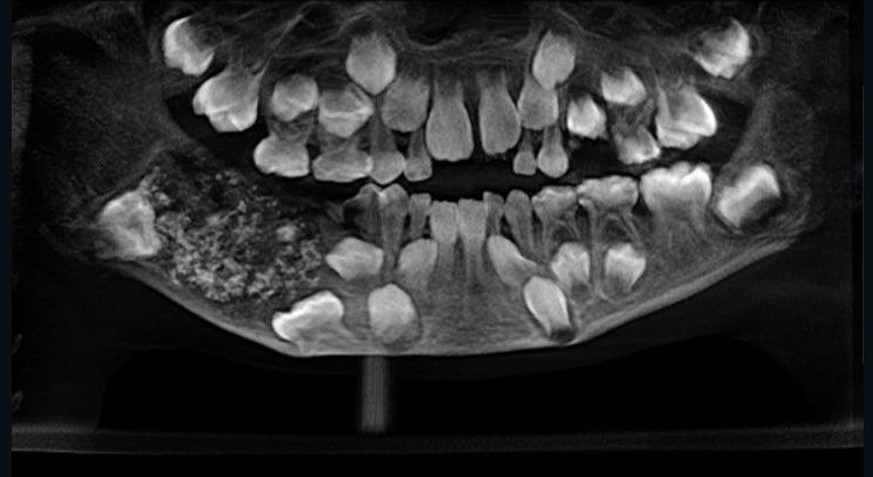

«Wir haben 526 Zähne in der Grössenordnung von 0.1 Millimeter bis 15 Millimeter entfernt», sagte Pratibha Ramani, Chefin der Fachabteilung im Spital Saveetha Dental College and Hospital in Chennai, am Freitag. Alle Zähne hätten Wurzel, Krone sowie Zahnschmelz gehabt.

Der Siebenjährige habe zuvor über Kieferschmerzen und Schwellungen geklagt, ohne dass die im rechten Unterkiefer versteckten und nicht sichtbaren Zähne entdeckt worden seien, sagte Ramani weiter. Demnach litt er an einem sogenannten Odontom, einer gutartigen Geschwulst, die viele rudimentäre Zähne enthalten kann. Ungewöhnlich ist jedoch die Zahl. 2014 waren einem Teenager im westindischen Mumbai nach Angaben des Spitals 232 Zähne entfernt worden.

Röntgenbilder des Spitals in Chennai zeigen eine Ansammlung von Zähnen. Der Junge habe nach dem Eingriff nun eine «gesunde Anzahl von 21 Zähnen» und sei drei Tage nach der Operation entlassen worden. Der fünfstündige Eingriff erfolgte bereits am 11. Juli, wie das Spital weiter mitteilte.